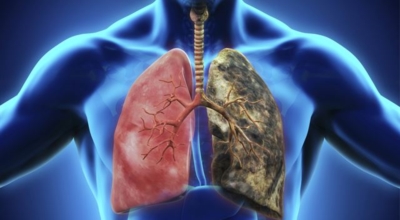

폐렴은 폐의 세기관지 이하 부위 특히나 폐포에 발생한 염증입니다. 폐렴을 유발하는 병원 미생물은 우리의 생활환경에 존재하고 있고 몸 안에 서식합니다. 폐렴의 가장 흔한 까닭은 미생물인 세균이나 바이러스이고, 드물게 곰팡이에 의한 감염이 있을 수 있습니다.

미생물에 의한 감염성 폐렴 이외에 화학물질이나 구역질물과 같은 찌꺼기의 흡인, 가스의 흡인, 방사선 치료 등에 의해 비감염성 폐렴이 발생할 수 도 있어요. 폐렴구균은 노인을 감염시키는 세균으로 가장 많이 알려져 있죠. 그리고 폐렴은 일상적인 예방이 중요합니다. 손씻기, 양치질, 구강 케어 등을 습관화하고 주변 환경을 깨끗하게 해주고 위생 관리를 해서 폐렴을 방지할 수 있답니다.